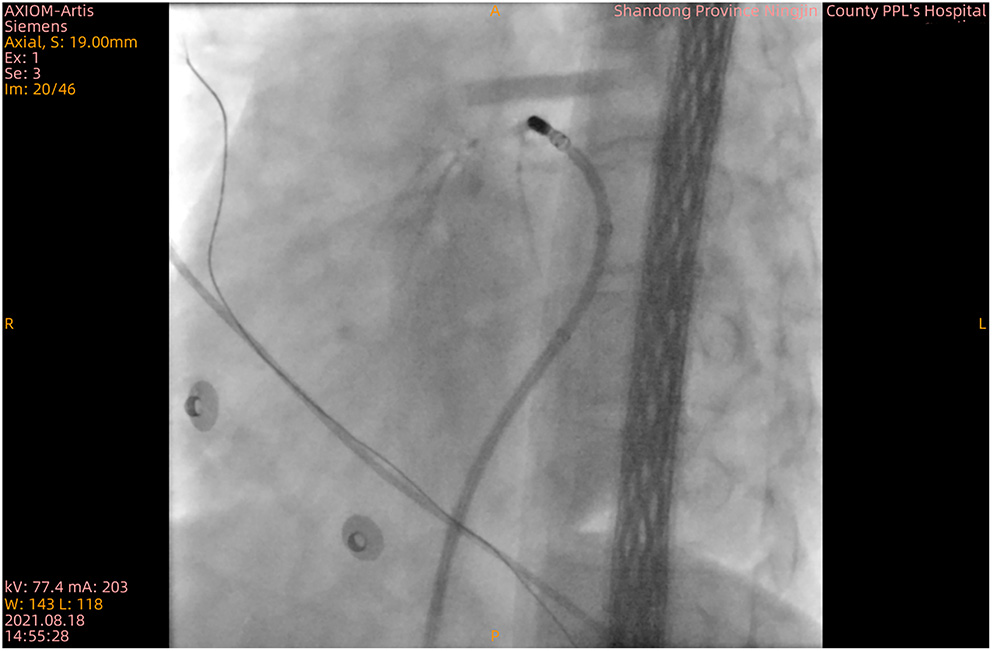

Figure 2

X-ray confirming blood circulation in the great cardiac vein.

After discontinuation of all anti-arrhythmic medications for at least five half-lives, the patient underwent an electrophysiologic study under local anesthesia, and then mapping and ablation were performed with an 8-Fr decapolar catheter (SmartTouch, Biosense Webster, United States). PVCs were demonstrated in the great cardiac vein, and then the catheter was positioned (Figure 2 and Supplementary Video 1). The impedance at the ideal mapping position immediately increased to about 300 Ω, and radiofrequency energy was delivered at a power of 25 W with a saline irrigation flow velocity of 17 ml/min. After 20 s, an X-ray revealed that the catheter was impacted at this position (Supplementary Video 1). After several failed attempts to extract the catheter, the abnormality was considered to be vasospasm. A venogram was immediately manipulated to confirm great cardiac vein flow and rule out cardiac tamponade (Figure 2). Saline was simultaneously injected at a rate of 1 ml/min via the intracoronary vein. The angiography showed pericardial effusion. Pericardiocentesis was performed by extracting a 40 ml colorless transparent liquid, which appeared to be saline that was effused from the catheter. Approximately, 4 min after intracoronary injection of nitroglycerin (200 ug), the vasoconstriction was rapidly relieved (Supplementary Video 2). An angiogram via the coronary sinus was performed, which showed no signs of exudation, suggesting effusion of pericardial fluid from the catheter but not perforation. Mapping and ablation were continued, with vasoconstriction ceased to persist, and the patient ultimately converted to sinus rhythm twice, each time with 60 s. The procedure was finalized uneventfully.